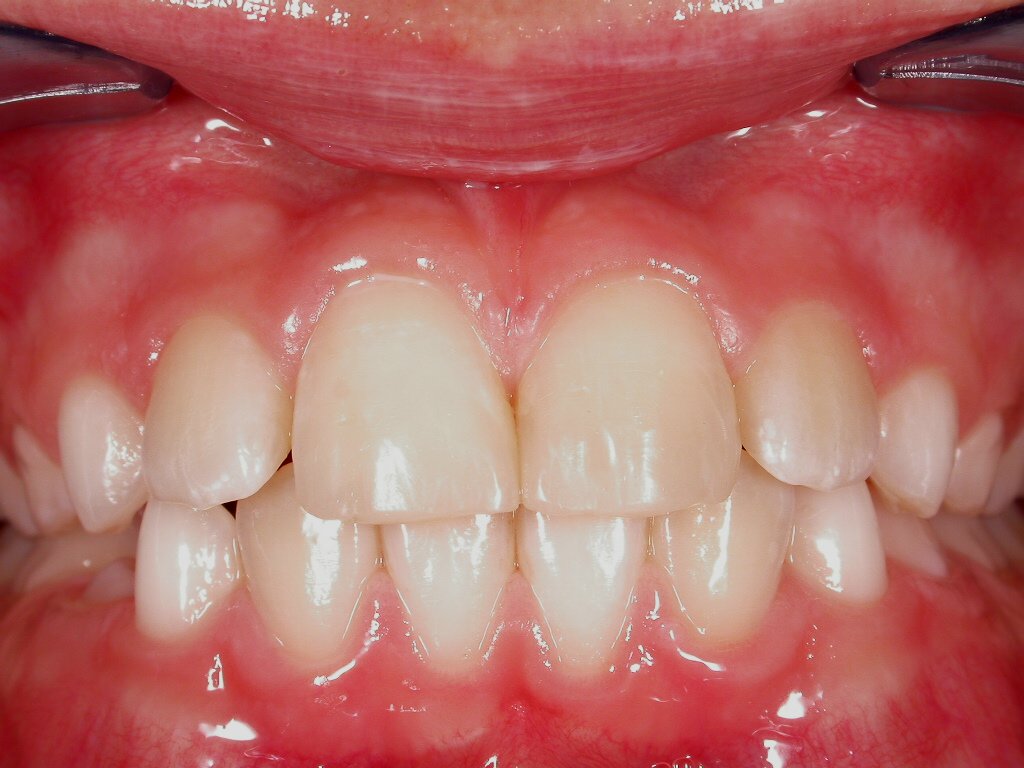

Teilweise Nichtanlage bleibender Zähne mit teilweise noch vorhandenen Milchzähnen, abgesunkener, lückiger Bisslage

Vorher: Teilweise Nichtanlage bleibender Zähne mit teilweise noch vorhandenen Milchzähnen, abgesunkener, lückiger Bisslage

Komplettbehandlung mit Bisshebung, Setzen von Implantaten als Ersatz für die Milchzähne, Schaffen einer völlig neuen, ästhetischen Gesamtsituation mit vollkeramischen Kronen und Brücken

Nachher: Komplettbehandlung mit Bisshebung, Setzen von Implantaten als Ersatz für die Milchzähne, Schaffen einer völlig neuen, ästhetischen Gesamtsituation mit vollkeramischen Kronen und Brücken